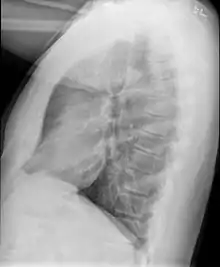

Causes include breathing in toxic fumes, respiratory infections, connective tissue disorder or complications following a bone marrow or heart-lung transplant.[1] Symptoms may not occur until two to eight weeks following toxic exposure or infection.[1] The underlying mechanism involves inflammation that results in scar tissue formation.[1] Diagnosis is by CT scan, pulmonary function tests or lung biopsy.[1] A chest X-ray is often normal.[4]

Bronchiolitis obliterans is often diagnosed based on the symptoms of obstructive lung disease following lung injury. The definitive diagnosis is through biopsy, but due to the variable distribution of lesions, leading to falsely negative tests, and invasive nature of this procedure it is often not performed.[6][11] Several tests are often needed to diagnose bronchiolitis obliterans, including spirometry, diffusing capacity of the lung tests (DLCO), lung volume tests, chest X-rays, high-resolution CT (HRCT), and lung biopsy.[11][4]

Medical imaging

Early in the disease chest radiography is typically normal but may show hyperinflation.[6] As the disease progresses a reticular pattern with thickening of airway walls may be present.[4][6] HRCT can also show air trapping when the person being scanned breathes out completely; it can also show thickening in the airway and haziness in the lungs.[11] A common finding on HRCT is patchy areas of decreased lung density, signifying reduced vascular caliber and air trapping. This pattern is often described as a "mosaic pattern", and may indicate bronchiolitis obliterans.[6]